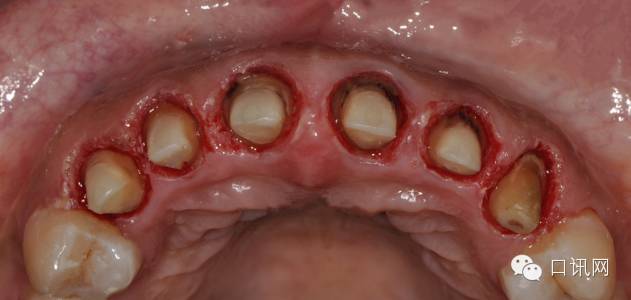

处理:11,12,13,21,22,23拆除原烤瓷冠,重新根管治疗,瘘管愈合后,纤维状修复,水激光切除牙龈,牙体预备,临时冠修复,硅橡胶取模,氧化锆烤瓷修复执业助理医师,待遇优厚,底薪加提成

水激光切除牙龈

牙体预备,精修,抛光按照科学发展理念与时俱进,适应时代需要,